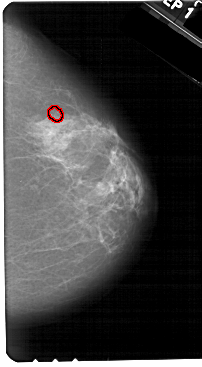

A_1328_1.RIGHT_MLO

RIGHT_MLO LINES 5491 PIXELS_PER_LINE 3046 BITS_PER_PIXEL 12 RESOLUTION 43.5 OVERLAY

FILE: A_1328_1.RIGHT_MLO.OVERLAY

TOTAL_ABNORMALITIES 1

ABNORMALITY 1

LESION_TYPE CALCIFICATION TYPE PLEOMORPHIC DISTRIBUTION CLUSTERED

ASSESSMENT 4

SUBTLETY 5

PATHOLOGY BENIGN

TOTAL_OUTLINES 1

BOUNDARY